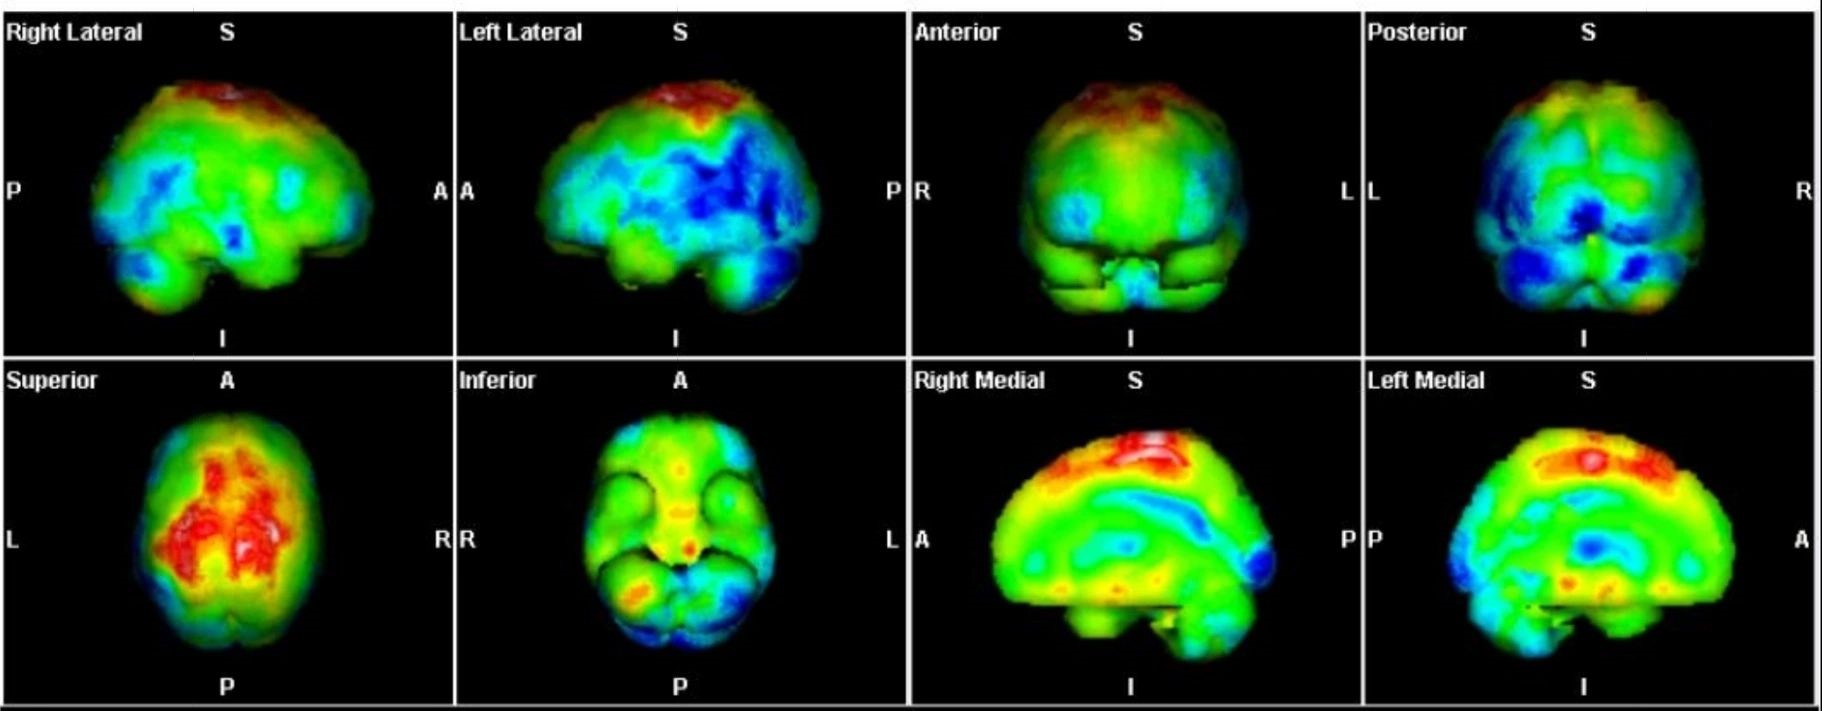

Με τη SPECT‑CT ποσοτικοποίηση υπολογίζουμε απορροφούμενες δόσεις σε όγκους και όργανα‑στόχους (νεφροί, σιελογόνοι, ήπαρ, μυελός κ.ά.). Αυτό:

Σημείωση: Σύμφωνα με πρόσφατες κλινικές εργασίες/σειρές ασθενών – όπως οι LUMEN‑2 (για ΝΕΤ) και νεότερες μελέτες σε PSMA‑στόχο – η ποσοτική δοσιμετρία συσχετίζεται με την έκβαση και βελτιώνει τον θεραπευτικό σχεδιασμό.

Με βάση τα σύγχρονα Guidelines όλων των διεθνών ογκολογικών εταιρειών η μεταθεραπευτική απεικόνιση είναι προαπαιτούμενο για την έναρξη-συνέχιση της θεραπείας και το βέλτιστο αποτέλεσμα αυτής.

ΠΟΣΟΤΙΚΗ ΕΚΤΙΜΗΣΗ – ΜΕΤΡΗΣΗ ΟΓΚΟΥ ΝΟΣΟΥ